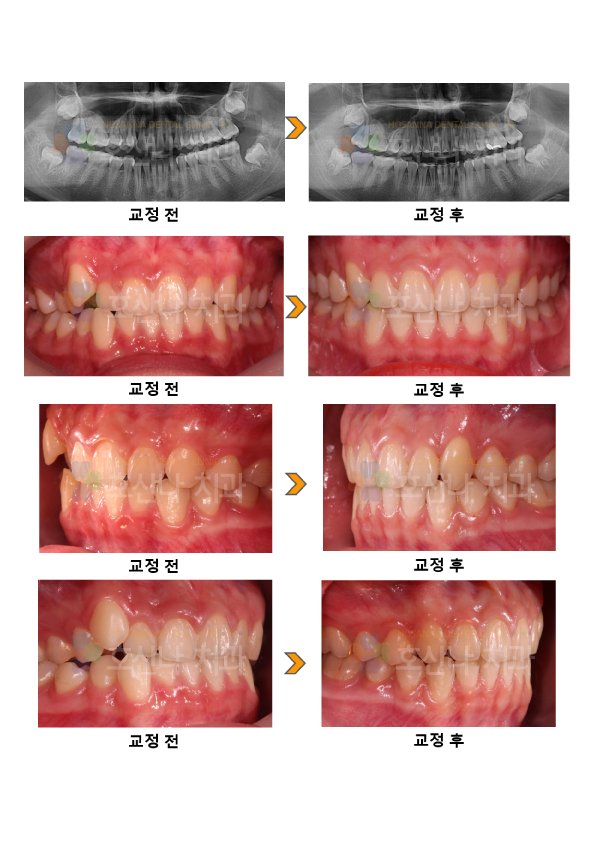

교정비발치 확장 크라우딩 시술 증례

< 비발치 확장 크라우딩 개선  >

1. 치료대상

13y 10m

2. 교정치료이유

덧니 개선 원함

3. 환자분 c.c

① 치아가 잘 안 맞물려요.

② 입이 너무 들어가지 않았으면 좋겠어요

4. Dr.Koo Memo

덧니를 주소로 내원하였습니다.

초진 안모에서 입술이 얇고 정면, 측면에서 돌출을 보이지 않고 오히려 오목한 안모를 보였으며 치아가 배열될 공간은 부족하지만 발치는 가능한 피하는 것이  좋았습니다.

부모님도 최대한 발치 하지 않길 원하셔서 비발치 확장을 계획 후  RPE 와 BH 를 통해 확장하였고  damon 브라켓을 사용하였으며 1년이 안 되는 단기간에  마무리 되었습니다.

5.교정기간

10m